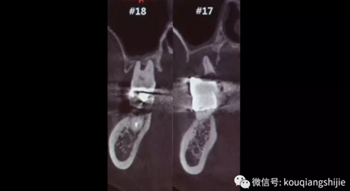

這個患者在2012年的時候#17已經(jīng)是需要拔除的情況,但是因為患者要求保留,所以我們進行保守治療

4年后患者再次就診,要求拔出

這時候我們可以看到患牙周圍已經(jīng)沒有任何骨壁。

我們可以看到#17,18的牙周炎非常嚴重

從CT上我們可以看到骨破壞非常嚴重